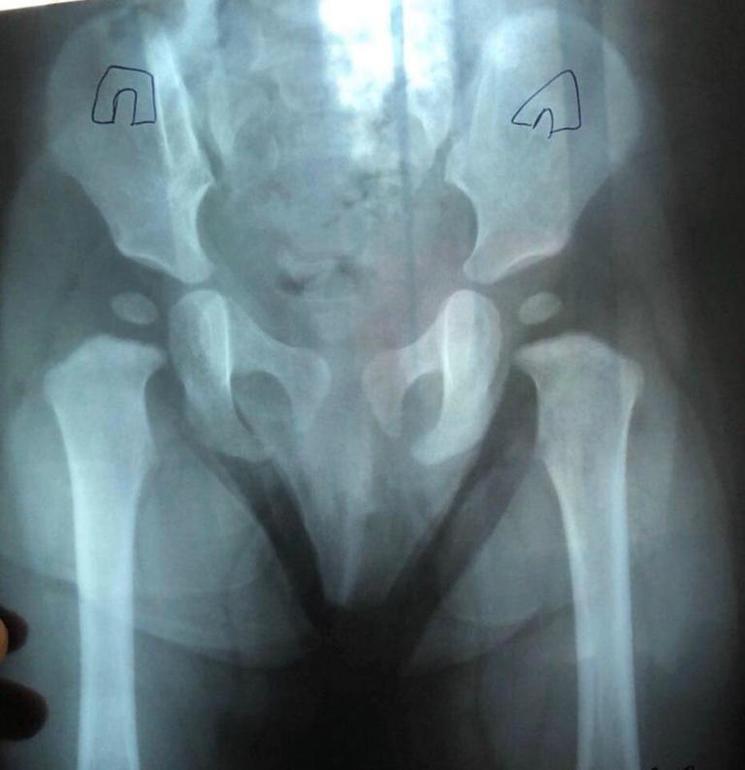

Помогите расшифровать снимок ТБС, ребенку 1,1 год

Сделали ребенку 1,1 год рентген на ТБС и есть подозрение на дисплазию, мнения врачей разделились. Я в отчаянии

Складки не симетричны, ребенок не ходит

Ножки развоодятся хорошо. Когда сидит, обычно подгибает одну ногу под себя, а другую выпрямляет.

Говорят есть латеральное смещение головки бедра (в основном правого)

И разорвана линия Шентона (тоже справа)